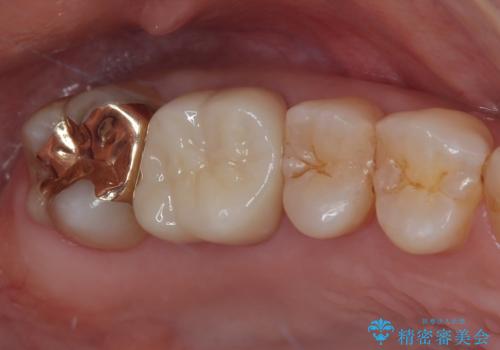

- 左上の前から5番目の金属の詰め物(メタルインレー)が取れたとのことで来院された患者様です。一時帰国中とのことで短期間での治療を希望されていました。土台はファイバーコアがしっかり入っていたため、そのまま利用することにしました。根管治療は症状もなく、レントゲン上でも病変を認めないため患者様と相談して根管治療を行わないことにしました。拡大鏡の視野下において、虫歯を除去して元々の詰め物の範囲も大きいためオールセラミッククラウンに適した形に整えました。

型どりは、シリコーン印象材にて印象しています。

適合もよく、機能的に問題もなく、見た目も満足されていました。